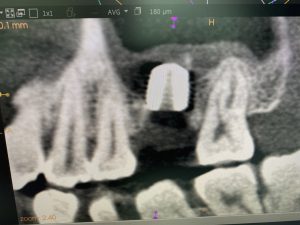

本日は左上6番、ソケットリフト併用のインプラントオペから始まりました。

某スーパードクター発案。人工骨を使わず洞低膜挙上する手法です。真似してやってます

添付画像の通り、裾野も拡く5ミリ位挙上出来バッチリ

白色に見えるのは、塊のコラーゲン製剤

挙上空間スペースは自家骨に置換されるので、より安定性増し

更には術後の副鼻腔粘膜の肥厚がごく僅かに抑えられます!